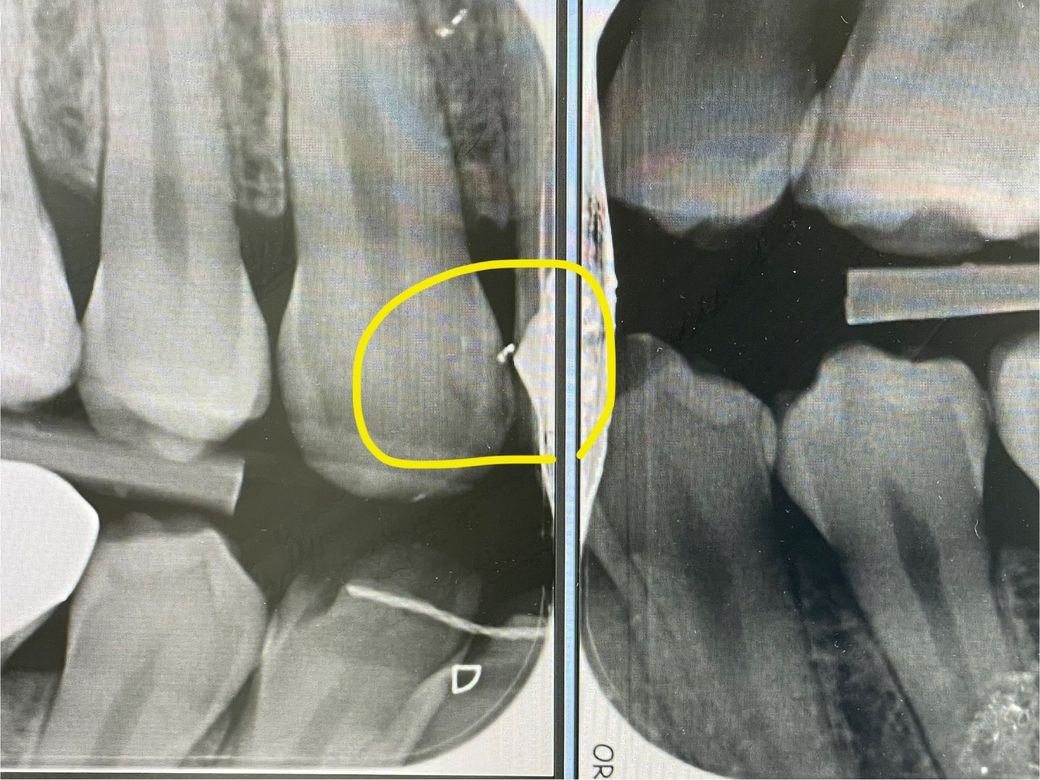

검진하며 엑스레이 찍고보니 앞니 하나 예전에 레진으로 떼운것과 치아 사이에 공간이 생긴것 같네요. 충치일수 있나요? 당장 치료 해야 하는지 궁금합니다. 해외 살고있어서 고민됩니다…NHS 치과 기술 안좋기로 유명합니다

현재 틈이 있는 경우 레진이 탈락되었을 가능성이 높으며, 이 경우 틈사이로 음식물, 세균이 들어가면 2차 충치가 발생할 가능성이 높아집니다.

현재 통증 시림과 같은 불편감이 없는 경우 당장 급하지는 않지만 가급적 빠른 시일내에 치료를 하는 것이 좋습니다.

지금 증상이 없다면 하방 충치의 양상이라기보다는 레진 수복 과정에서 생기는 미세갭일 가능성이 있습니다